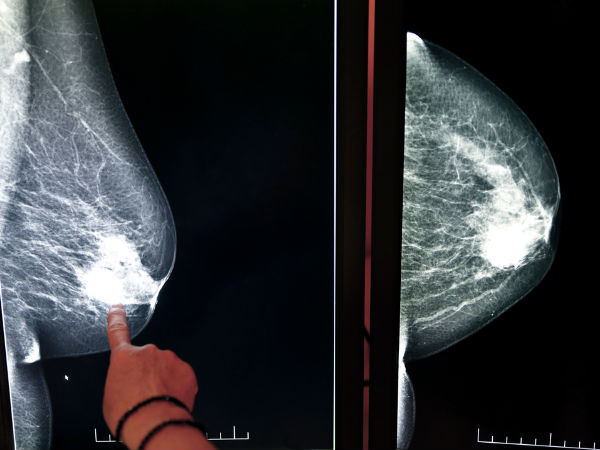

பெண்கள் மார்பகத்தை பற்றி அறியப்படாத 10 உண்மைகள் - வினா, விடைகள்!

பெண்கள் தங்களின் உடல் மீதே மிகுந்த அறியாமை கொண்டுள்ளனர். இதுதான் அவர்களுக்கு பல்வேறு கஷ்டங்களை தந்து கொண்டிருக்கிறது. அதிலும் பெண்களை அதிகம் தாக்கும் மார்பக புற்றுநோய் போன்றவற்றை பற்றி தெரிந்து வைத்தி

பெண்கள் தங்களின் உடல் மீதே மிகுந்த அறியாமை கொண்டுள்ளனர். இதுதான் அவர்களுக்கு பல்வேறு கஷ்டங்களை தந்து கொண்டிருக்கிறது. அதிலும் பெண்களை அதிகம் தாக்கும் மார்பக புற்றுநோய் போன்றவற்றை பற்றி தெரிந்து வைத்திருக்க வேண்டும். பெண்களுக்கு தங்கள் மார்பகங்களை பற்றி கண்டிப்பாக அதிக கவனமும், விழிப்புணர்வும் மிக அவசியமானது. இந்த பதிவில் சற்றே வித்தியாசமான வினா - விடைகளுடன், உங்கள் மார்பகங்களை பற்றிய ஆரோக்கியமான விஷியங்களை தெரிந்து கொள்வோம்.